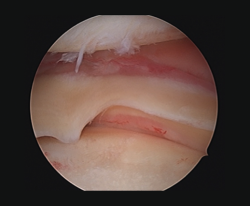

Other diagnostic tests are radiographs under stress varus conditions. We can find indirect radiological signs such as Segond fracture and the arcuate sign. MRI is of great help. Gelber et al. recently reported that over 80% of a group of world experts in the treatment of posterolateral angle injuries agree on the usefulness of MRI in the diagnosis of these lesions(17). Lastly, arthroscopy can offer additional information in the surgical cases (Figure 2).

Figure 2. Arthroscopic view through the anterolateral port of damage to the meniscus-popliteal ligaments (*) at the level of the popliteal hiatus, leaving the tibia exposed (T). P: tendon of the popliteus muscle. Right knee.